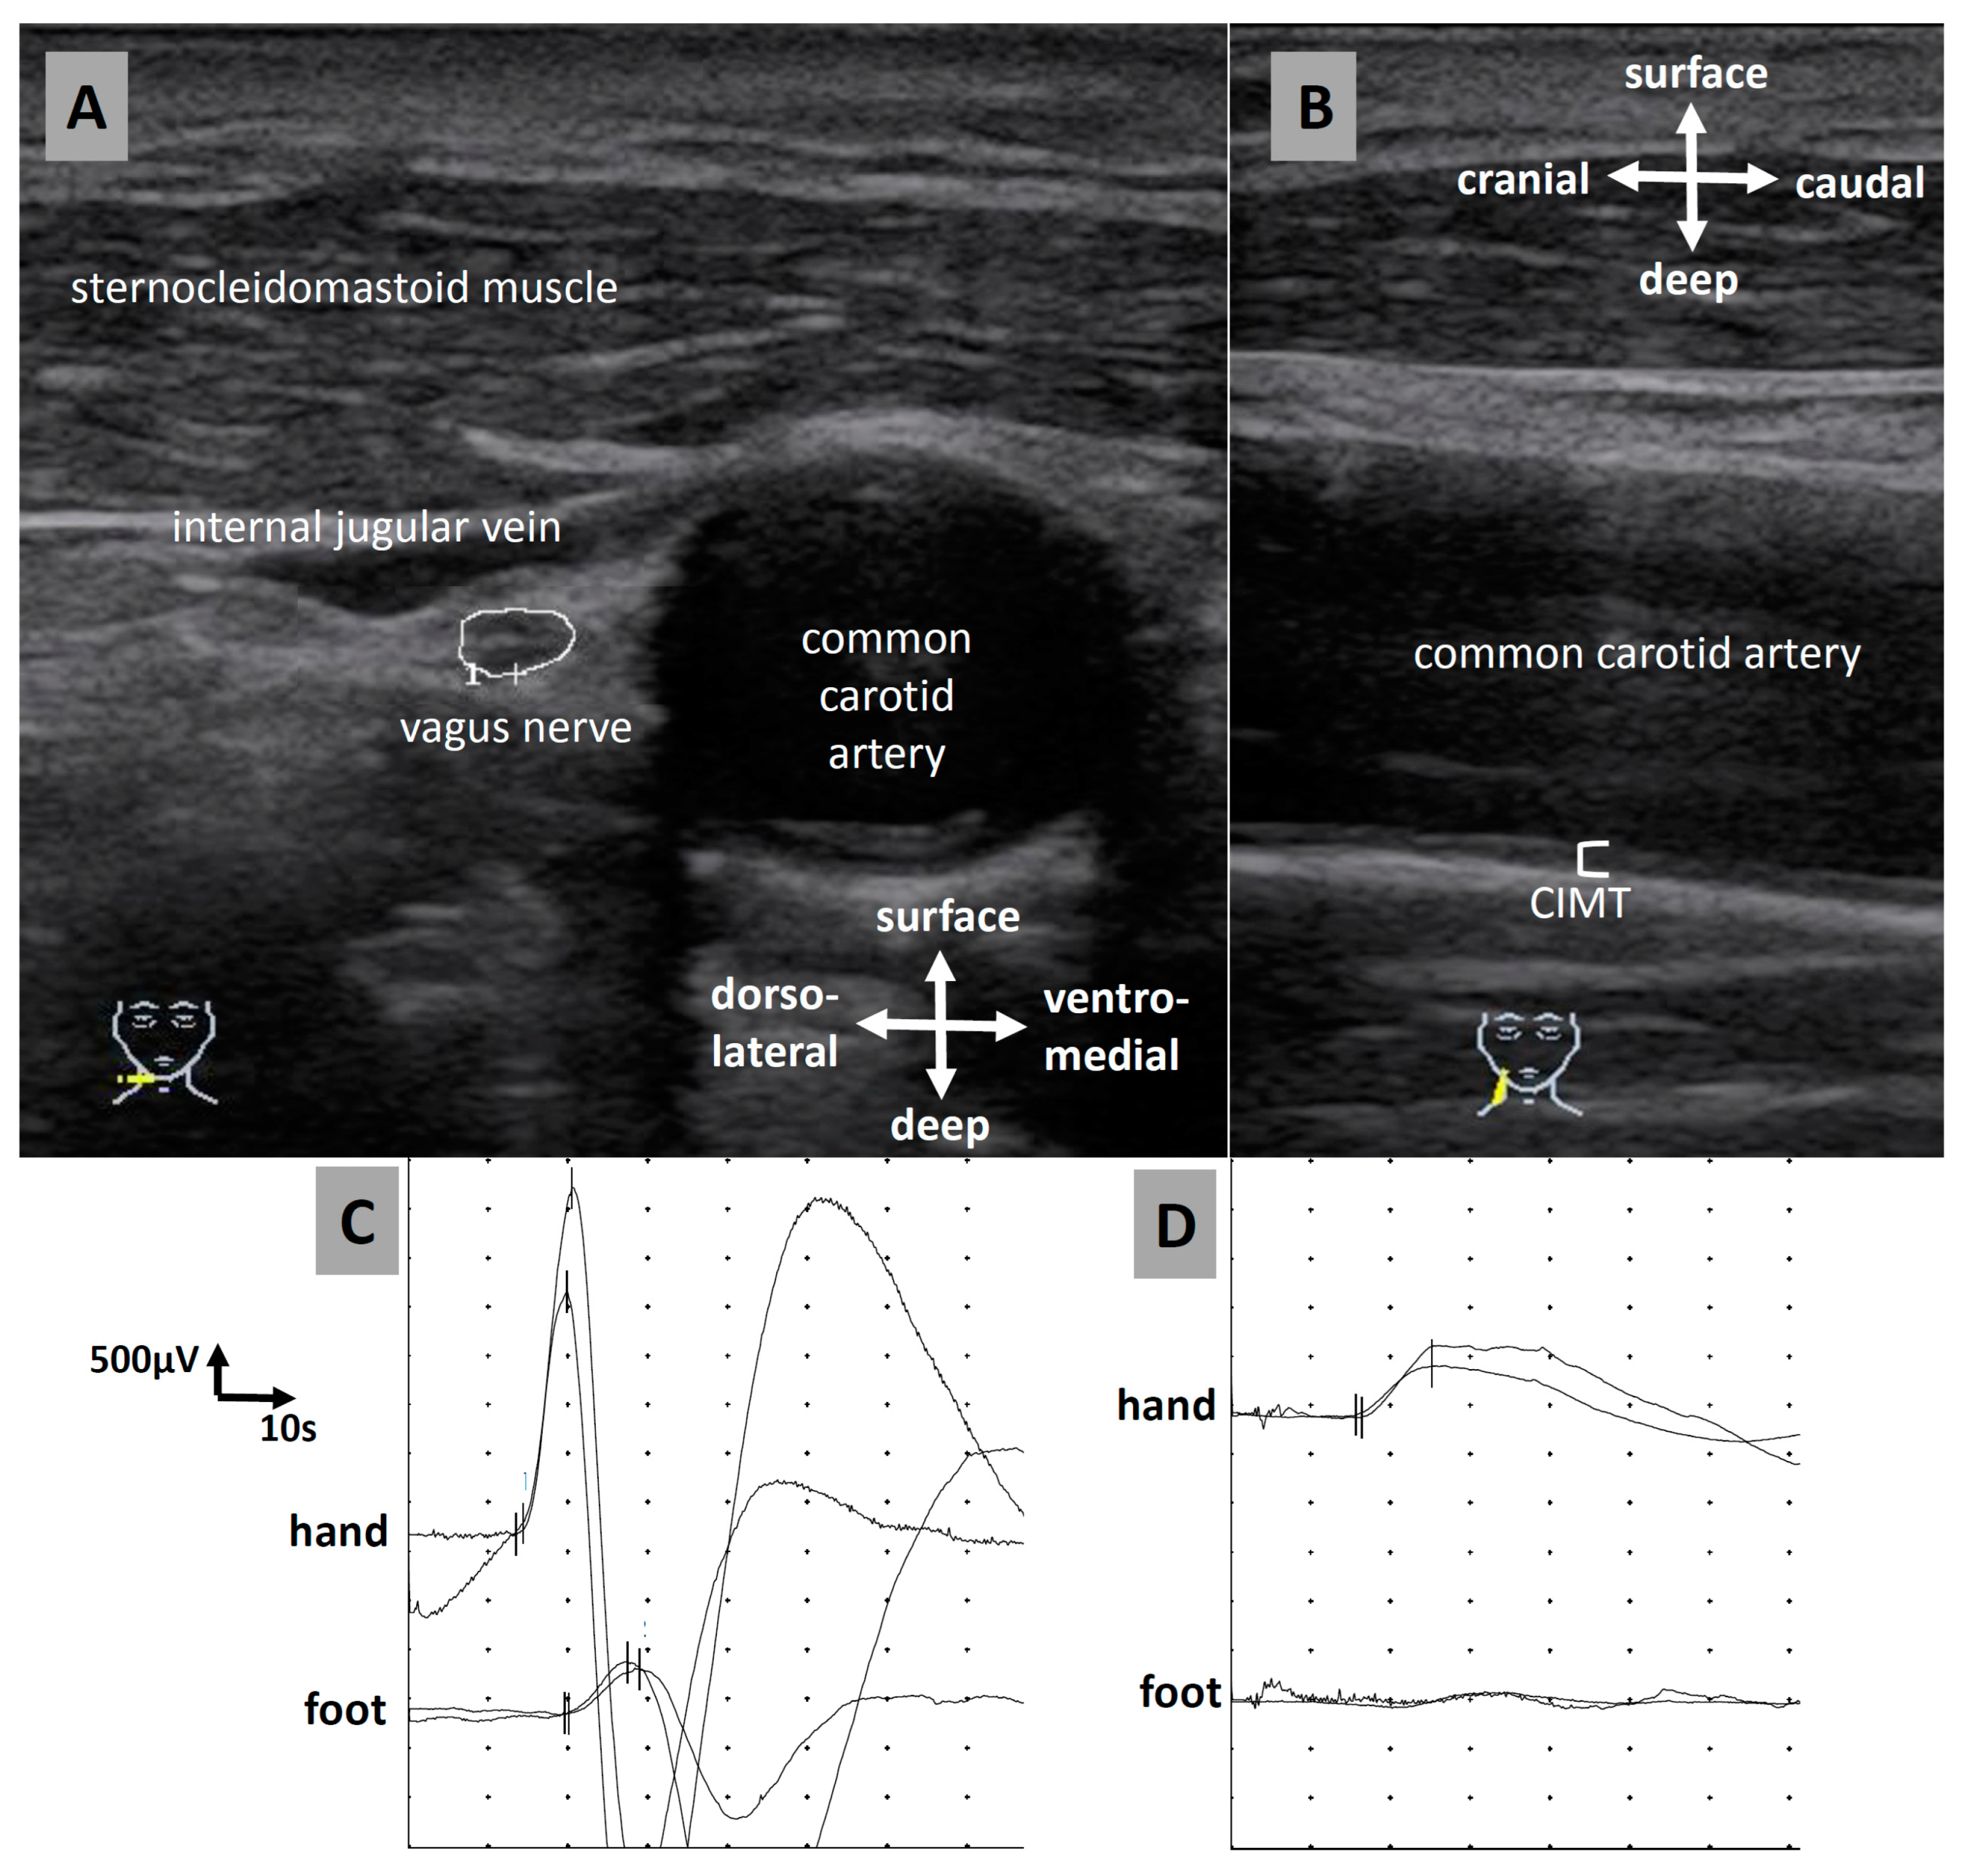

2.3. Ultrasound

2.4. Sympathetic Skin Response and Nerve Conduction Studies